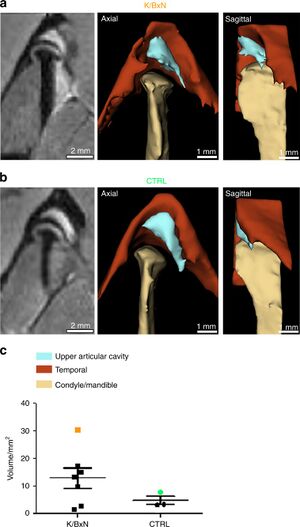

- 1.60 Temporomandibular Joint Damage in K/BxN Arthritic Mice

- 1.61 Synchrotron Radiation-Based Reconstruction of the Human Spiral Ganglion: Implications for Cochlear Implantation